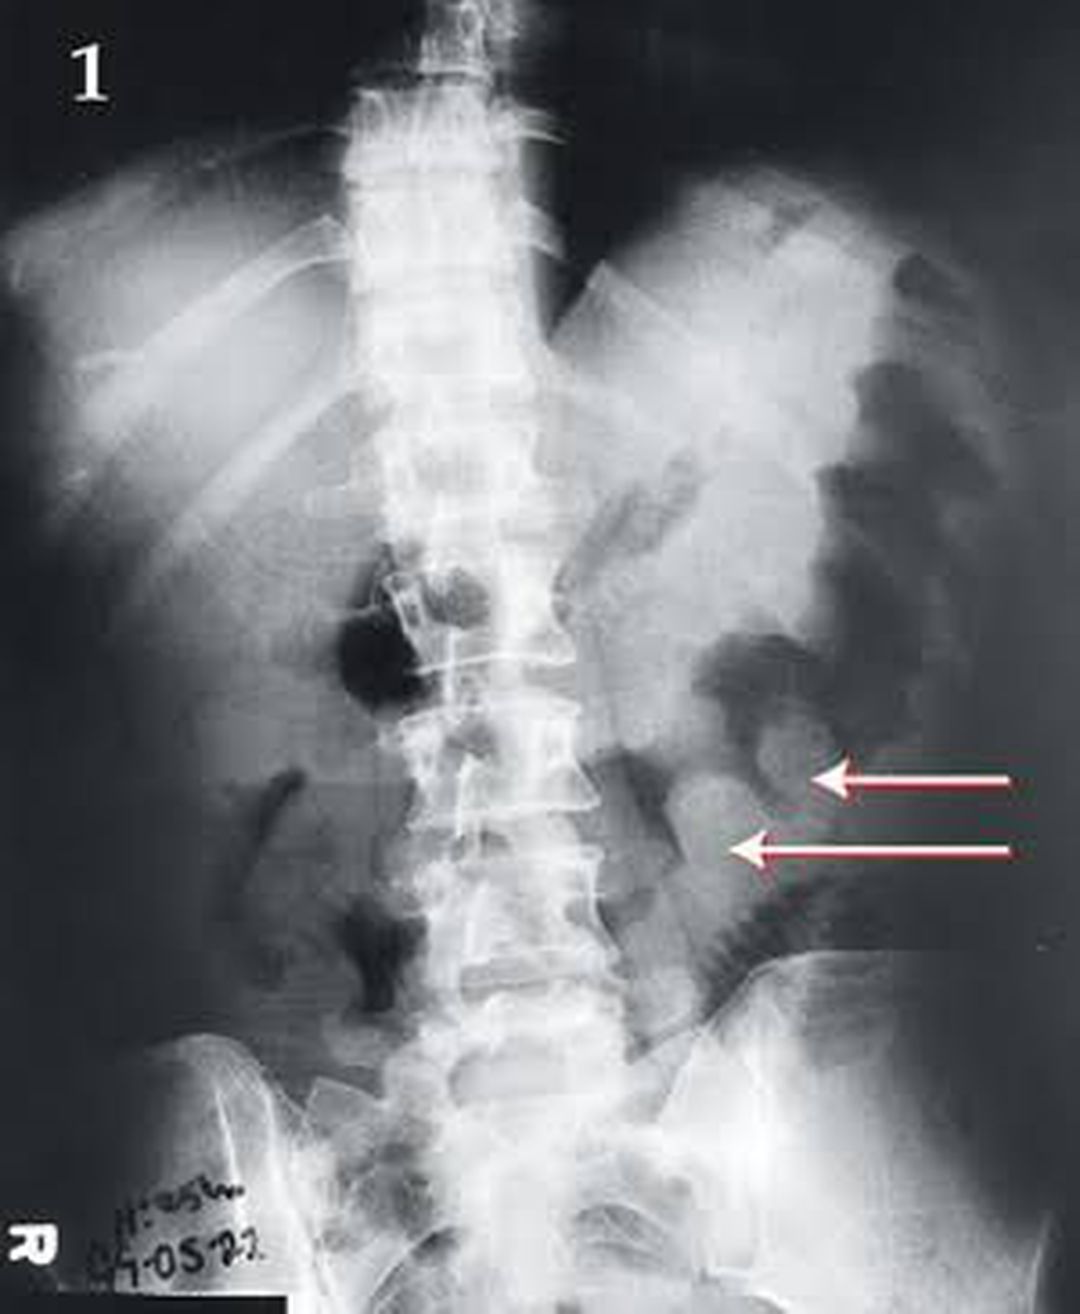

A 39 year old female with AIDS presented to OPD with a history of watery Diarrhea, nausea and vomiting for four days. The patient was afebrile and a clinical examination revealed distended abdomen without rebound tenderness. Labs were normal and stool cultures were negative. A CT scan and abdominal x-ray was conducted, which showed thumbprint sign. A suspicion of pseudomembranous colitis was made. Later, colonoscopy was also conducted which showed a colon having yellow plaques, thus confirming the diagnosis. The patient was administered oral metronidazole and improved subsequently. Ref: Moishe Liberman, Chris Labos and Jeff Wiseman Med J Aust 2003; 179 (2): 107. || doi: 10.5694/j.1326-5377.2003.tb05448.x